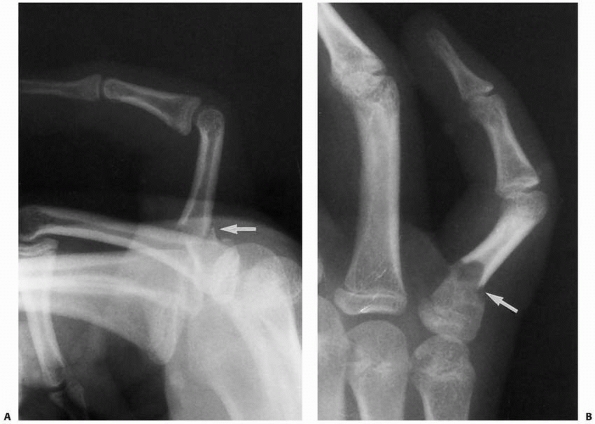

![]() |

FIGURE 8-5

The straight-method of assessing alignment about the MCP joint. The long axes of the metacarpal and proximal phalanx should align, as they do in this normal hand (A). If there is a fracture in the proximal phalanx, as in this patient’s opposite or injured hand (B,C), the axes will not be colinear (arrows). (Courtesy of Robert M. Campbell, Jr., MD.) |